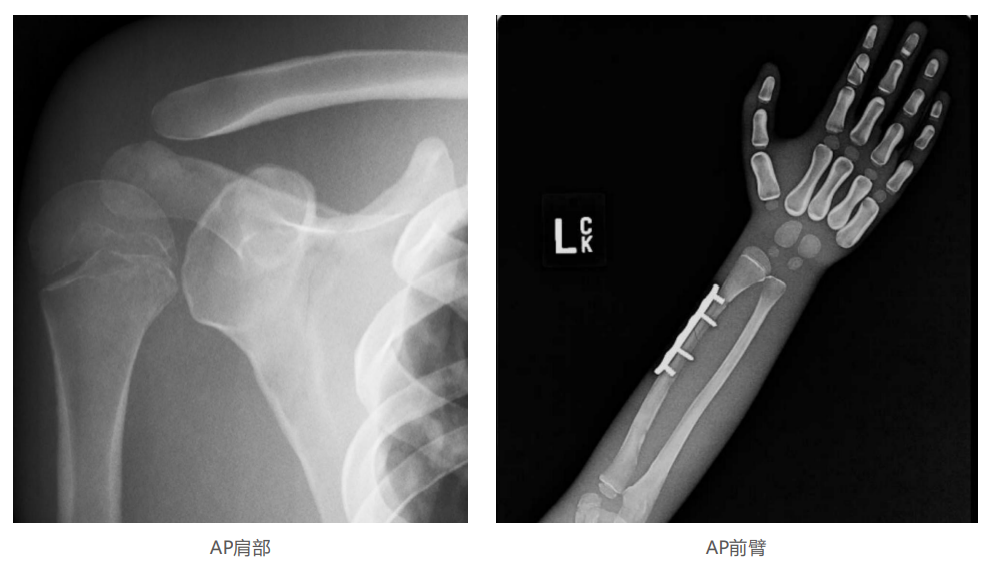

模体的大小和结构都代表了人体模体,使其便携和易于定位。包括头、胳膊和腿在内的整个身体。该系列包括六个部分的模体可单独或作为一个完整的集合。

右肢有伸直或弯曲两种配置。左臂和左腿可选伴有或不伴有内嵌骨折。

骨折版本包含最常见的人体骨折类型 ,包括胫骨扣带骨折和腓骨普通骨折;

第一跖骨骨折;桡骨切开复位骨折 ,第二中间趾骨常见骨折。组件由适当的聚氨酯和环氧材料制成,模拟人体组织的X射线衰减特性,用于诊断和治疗能量范围(50 keV - 25 MeV) 。 材料经久耐用 ,耐冲击,适合连续搬运。透明的软组织有助于解剖标志的视觉指示。

• 左附件五种最常见的骨折;